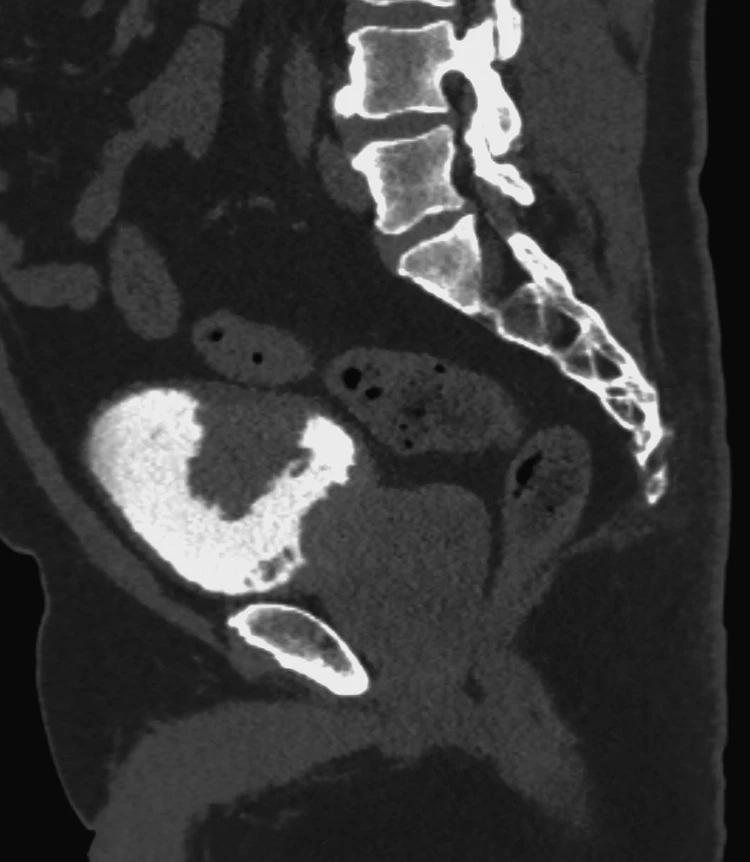

Пациент 27 лет. Две недели назад ударно-волновая литотрипсия. Неделю назад резкое повышение температуры тела, боли в боку. Повторная госпитализация. Установлен стент в левый мочеточник. Нарушения оттока мочи нет. На компьютерных томограммах левосторонний бактериальный нефрит, в верхнем полюсе левой почки – то, что иногда называют карбункул: воспалительный инфильтрат без формирования абсцесса (в англоязычной литературе называется нефрония). Принято решение продолжать антибиотикотерапию.